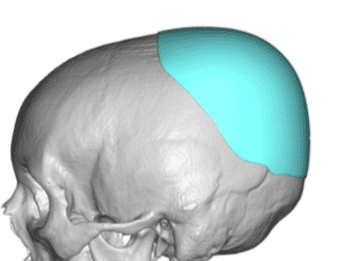

Desire for an improved head shape so that it looks rounder and not so peaked or sloped.

Placement of custom skull implant for parasagittal augmentation to create a rounder head shape. An example of what appears to be a high sagittal crest that is really low parasagittal skull areas.

Desire for an improved head shape so that it looks rounder and not so peaked or sloped.

Placement of custom skull implant for parasagittal augmentation to create a rounder head shape. An example of what appears to be a high sagittal crest that is really low parasagittal skull areas.